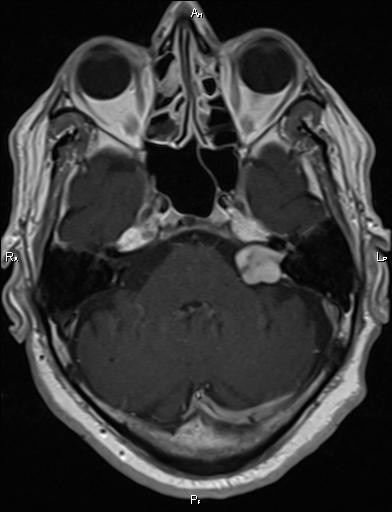

MRI Brain:

– This is an T1+c (CSF dark, white matter lighter than grey matter, contrast enhancement of mass) MRI of the cerebello-pontine angle, the gold standard investigation for this condition

– It shows a large contrast-enhancing mass at the L cerebello-pontine junction, with a tail extending into the internal acoustic meatus

Diagnosis: This is a L sided vestibular schwannoma (acoustic neuroma)